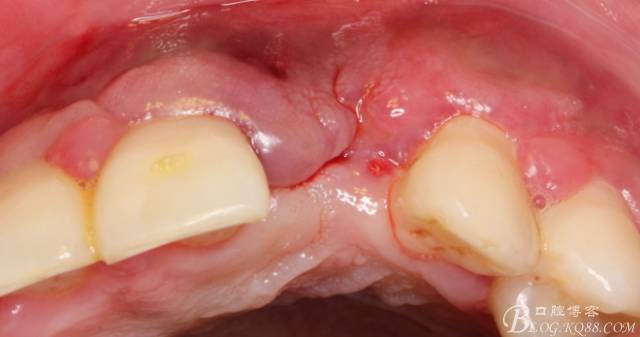

事實(shí)證明,我的做法沒(méi)有錯(cuò)誤,一個(gè)月后,軟組織健康愈合。鄰牙軟組織沒(méi)有退縮。